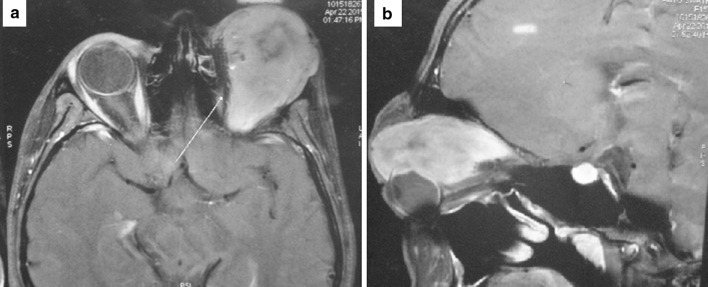

Clinical examination revealed a large firm, non-pulsatile, non-compressible and mildly tender extra-ocular fleshy mass in the upper half of the left orbital cavity which resulted in proptosis and downward displacement of the left eye (Fig. 1). The skin over the left eyelid was stretched, edematous with prominent dilated veins. There were no ocular movements and the visual acuity in the left eye was restricted to perception of light. General physical examination, examination of the right eye and the rest of the head and neck was within normal limits. An MRI of the orbit showed an ill-defined, heterogenous mixed intensity lesion in the upper part of the left orbit involving the extraconal, conal and intraconal compartments with diffuse edema and dilated vessels in the left orbit. 28 mm of proptosis was noted. The fat planes between the mass and the superior rectus, superior oblique and the anterior parts of the lateral and medial recti were indistinct. The mass caused mild compression along the postero-superior surface of the left eye ball. An intermediate intensity lesion in the left eyeball extending along the optic disc was noted. The mass was seen abutting the supero-lateral surface of the retro-bulbar segment of the left optic nerve with loss of fat planes. Loss of fat planes was also noted between the mass and the left lacrimal gland. There was however no extension into the superior orbital fissure, optic nerve or any intracranial extension (Fig. 2a, b). A trucut biopsy of the lesion along with a review of the slides of the prior surgery was suggestive of a solitary fibrous tumor. The patient underwent an uneventful left orbital exenteration, which entailed removal of the entire orbit including the globe, upper eyelid and orbital contents. The area of the proposed exenteration incision was marked giving wide margins to the tumour and sparing the uninvolved lower eyelid. The dissection was further carried down through the periorbita to expose the orbital rim all the way up to the orbital apex with the aid of a periosteal elevator. Care was taken to avoid inadvertent penetration of the lamina papyracea into the ethmoid sinus air cells. A curved haemostat was used to clamp the tissue around the orbital apex while the exenteration specimen was cut and delivered anterior to the clamp. A frozen section confirmation of the apical stump tissue was done to ensure tumor free margins. The orbit was lined with a split-thickness skin graft after securing haemostasis and ensuring no cerebrospinal fluid leak. The patient is being planned for formal orbital prosthetic rehabilitation (Fig. 3a–c). The final histopathology confirmed the diagnosis of SFT, arising from the ciliary body of the left orbit resected with clear margins (Fig. 4a–d).

Fig. 2.

a, b MRI of the orbit showed an ill-defined, heterogenous mixed intensity lesion in the upper part of the left orbit involving the extraconal, conal and intraconal compartments